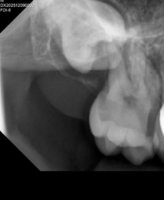

Umnikot ja butka sedmicata vo koren pa taka e vospaleno okolnoto tkivo,sega go reshavame vospalenieto pa ke pravime odnovo snimka i ke vidi oralniot hirurg sto ponatamu. Imam otok momentalno,zabite ne reagiraat nikako,nitu na toplo nitu na ladno nitu me bolat koga gi cetkam. Po kazuvanjata od stomatologot vospaleno e okolnoto tkivo,ne sum znaela deka 8 raste horizontalno i e impaktiran,ne sum pravela panoramska snimka dosega

Iskreno ne znam,samo znam deka za nijansa mi bese podobro. Ete ja i snimkata vo prilog,malku kropnata poradi licni podatoci